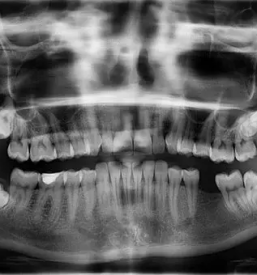

Pridite k ND dental zobozdravstvena dejavnost d.o.o., kjer vam je na voljo dobra zobozdravnica v Rogaški Slatini, na Savinjskem.

Strah pred obiskom zobozdravnika je precej pogost med otroci, prav tako pa ni redek med odraslimi. Pri nas se trudimo, da je obisk dobre zobozdravnice v RogaškiSlatini, na Savinjskem prijetna izkušnja, saj je naš cilj, da se pri zobozdravniku počutite dovolj prijetno, da ga redno obiskujete ter tako poskrbite za zdravje svojih zob in dlesni.

Za zdrav in lep nasmeh pridite k dobri zobozdravnici v Rogaški Slatini, na Savinjskem. Pri nas se zavedamo, da to pomembno vpliva na zdravje in počutje posameznika. Poskrbimo, da se boste prijetno počutili ob svojem obisku pri nas, kar lahko potrdi že mnogo naših pacientov in odličnih referenc širom naokoli.